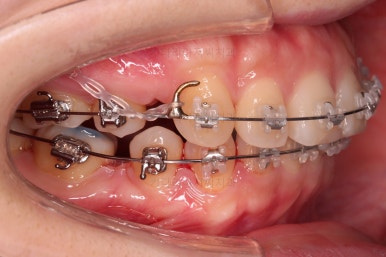

점점 치열이 가지런하게 되면서 발치한 자리도 조금씩 없어져가네요.

남는 자리는 입을 뒤로 넣는데 이용됩니다.

입이 얼마나 들어가고 있는지, 웃을 때 앞니 보이는 양, 중앙선 등 디테일한 부분들을 얼굴모습을 참고해서 평가를 해주고요.

당기는 방향 높이, 세기 등을 조절하면서 서서히 디테일을 맞춰갑니다.